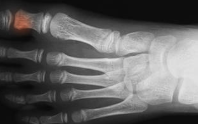

3. 발바닥 피로골절 – 한 지점이 눌리면 날카롭게 아픔

▷ 어떤 질환인가요?

발바닥 뼈에 **미세한 실금(스트레스 골절)**이 생긴 상태로, 격렬한 활동을 하거나, 갑작스럽게 운동량이 늘었을 때 발생합니다.

골절 부위는 주로 **중족골(발바닥 중앙~앞부분)**입니다.

▷ 특징

- 걷거나 뛸 때 발바닥 특정 부위가 콕콕 찌르듯 아픔

- 한쪽에만 발생, 지속적 통증

- 서 있을수록 통증 증가, 휴식 시 완화

- X-ray에서 잘 안 보이고 MRI나 골스캔으로 확인 가능